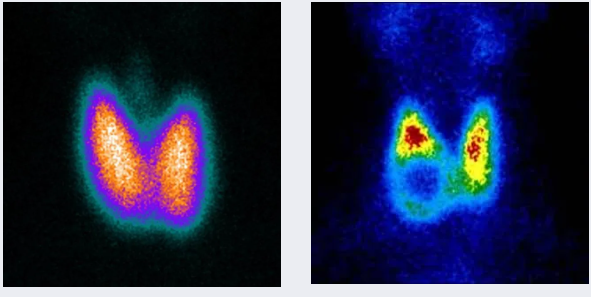

甲状旁腺显像

原发性和继发性甲状旁腺功能亢进的诊断与术前定位;异位甲状旁腺的诊断。

▲甲状旁腺显像